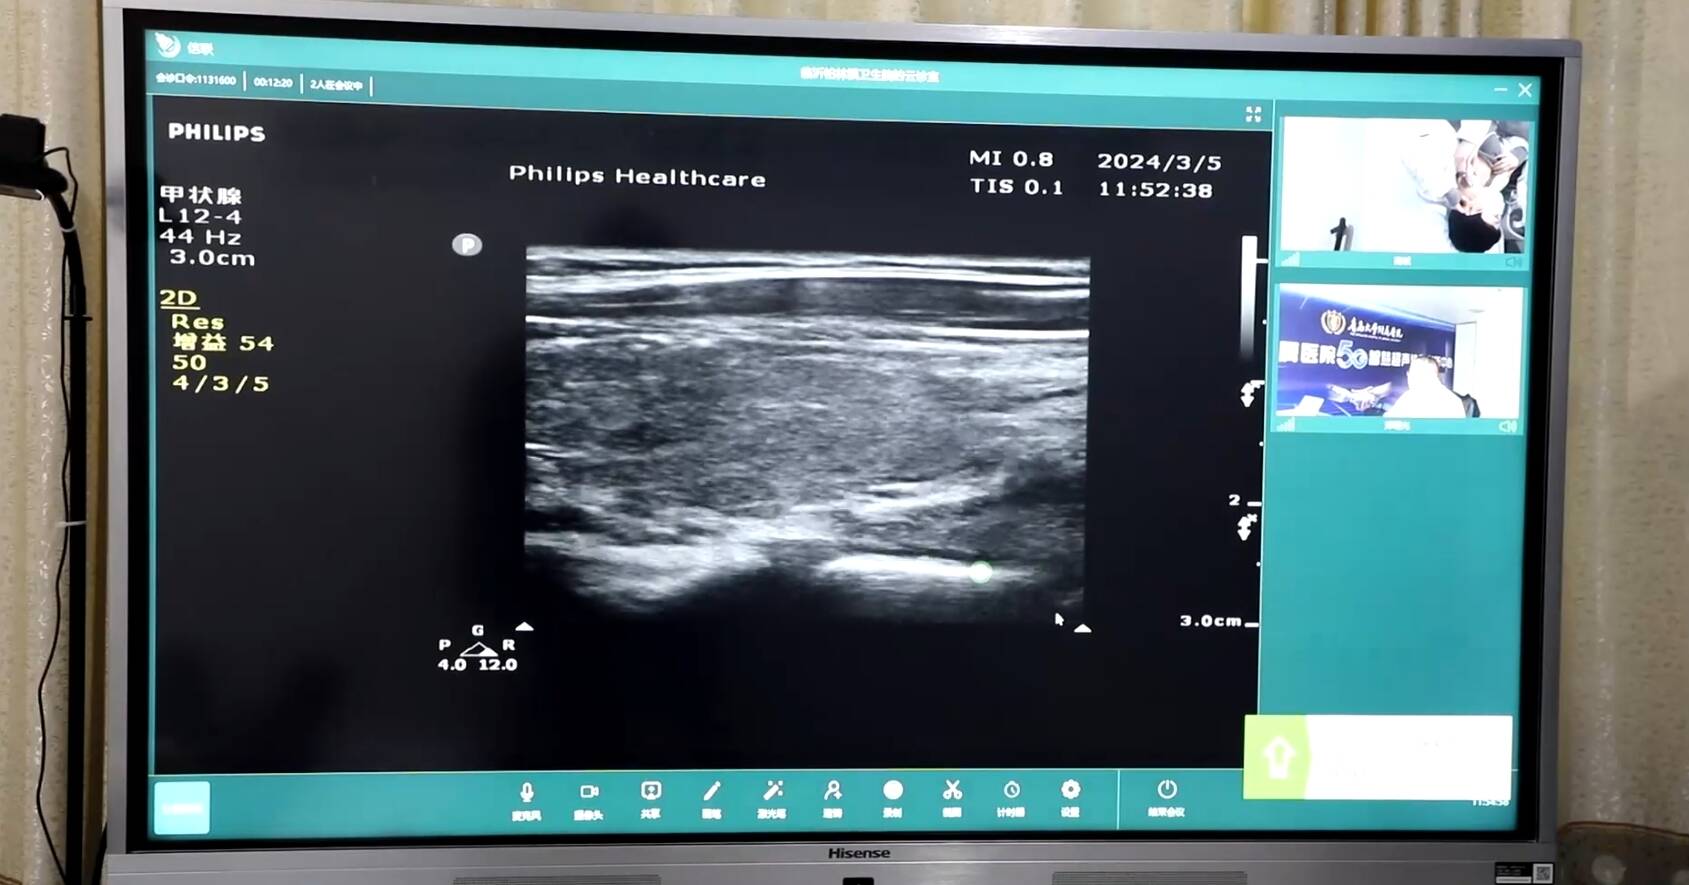

近日,家住平邑县柏林镇小娄村的蒋高平,他90岁高龄的奶奶因为常年下肢肿胀,疼痛难忍,无法直立行走,行动很不方便,他听说柏林镇卫生院通过视频连线就能和专家面对面,他很是高兴。来到5G远程诊疗室,专家通过详细介绍病情、汇报相关检查结果和5G智慧超声等方式,迅速给出了明确的诊断意见,并指导了下一步治疗方案。

远程医疗会诊打破了时间、空间、地域上的限制,使患者足不出县就可以享受到上级医疗专家高水平、高质量的服务,不仅帮患者避免了往返的奔波劳苦,降低了患者的就医成本,还为患者赢得了宝贵的就诊时间。